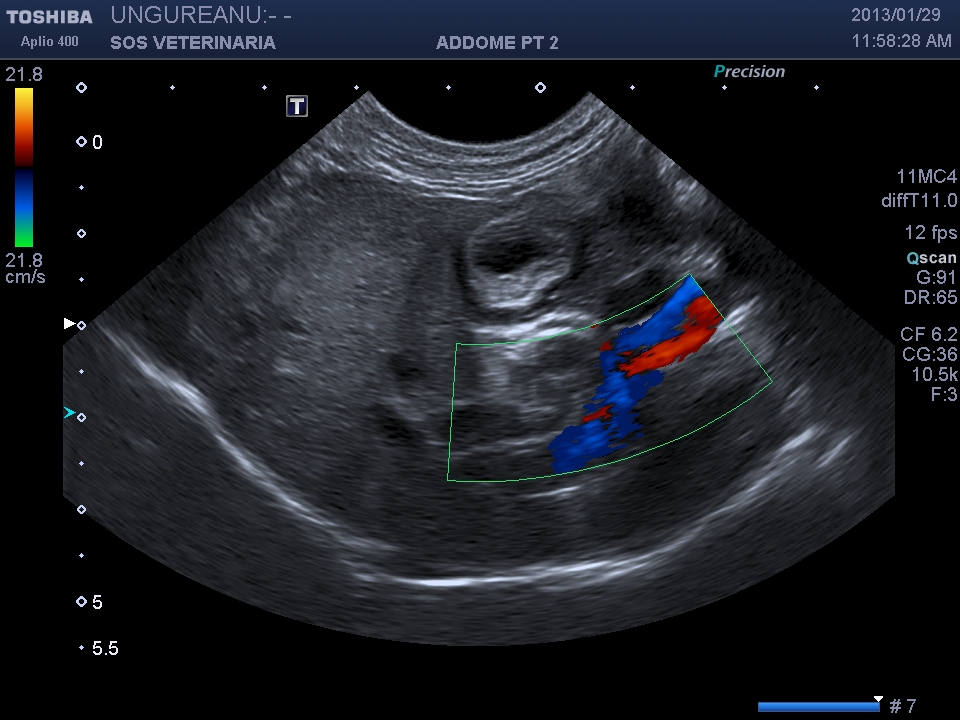

PROCESSO INFIAMMATORIO COLEDOCO E COLECISTE FORMAZIONE DI UN DIVERTICOLO ED ECTASIA DOTTO PANCREATICO

Gatta comune europea vive fuori e dentro casa pportata alla visita per anoressia e depressione rilevato ittero clinico

evidente la dilatazione e l’ispessimento   della parete  a carico di coleciste e coledoco con   formazione presfinterica di un ampolla ectasica simil diverticolo probabilemente secondaria alla cronicita’ del processo ,non si evidenziano ostacoli calcolotici o neoformazioni occludenti  il deflusso intra o extraluminali e a livello della papilla , il pancreas si presenta omogeneo ipoecogeno iperplastico trama vasale  ben evidenziabile .

Una  terapia di lunga durata con prednisolone alla dose di 0,5 mg/Kg sid comninata con marbofloxacillina e metronidazolo ha portato  dopo 4 settimane a risoluzione clinica e di laboratorio e ad un notevole miglioramento dell’imaging ,permane a distanza di 2 mesi  l’ectasia del dotto pancreatico e mofificazioni preampollari del coledoco con grado di distensione molto ridotto. Si e’ concluso  per un processo infiammatorio  possibile complesso colagioepatie ibd pancreatite (triatide)  con fenomeni iperplastici e fibrotici  a livello della papilla duodenale  e stenosi parziale del deflusso intraparietale duodenale ,tuttavia l’assenza di esami istopatologici non permette conclusioni certe eziopatogenetiche se non le evidenze riscontrate durante il decorso. Dopo due mesi il paziente alla sospensione dei farmaci mantiene la remissione.